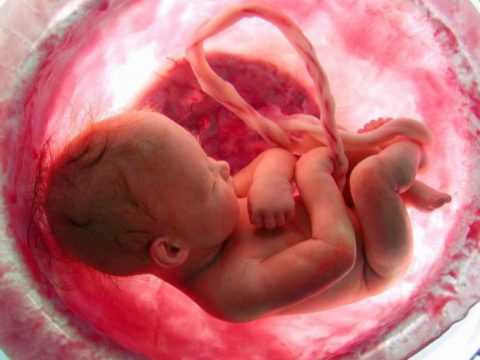

Диабетическая эмбриофетопатия — патологический синдром, который развивается у детей от матерей, больных сахарным диабетом, в результате поражения плода до 12 недели внутриутробной жизни. Включает характерные внешние признаки и пороки развития.

- Гипертрофический вариант. Развивается на фоне высокой гипергликемии, но без выраженных сосудистых осложнений. Рождается незрелый ребенок с большой массой тела.

| Макросомия | Большая масса тела ребенка (выше 4 кг при доношенной беременности).

Увеличение количества подкожной клетчатки. Проявляется образованием жировых складок на шее, туловище и конечностях. Нередко вес новорожденного достигает 5 кг и более (гигантский плод). |